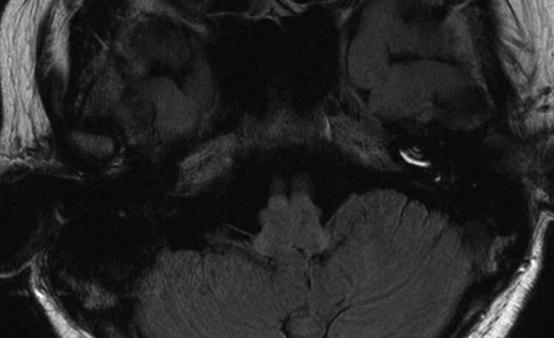

4、随着高分辨率核磁共振成像MRI的发展以及内耳局部给药技术的实现,在MD患者中观察到内淋巴积水已成为现实。2007年Nakashima等提出向MD患者鼓室中注射稀释的钆剂,24h后进行内耳三维磁共振成像液体衰减反转恢复序列3D-FLAIR MRI检查,由于造影剂可以经鼓室内侧壁渗透至外淋巴系统,而不能渗透至内淋巴系统,含有钆剂的外淋巴间隙显示为高信号,不含钆剂的内淋巴间隙显示为低信号,从而获得内淋巴积水的客观诊断依据。

操作流程:目前有采用经咽鼓管投药和经鼓膜投药法,相对后者成功率更高,操作也更简单。钆喷酸葡胺注射液与生理盐水以1:7比例混合稀释,加工过的22号针经鼓膜注射0.5ml至鼓室。嘱患者保持患耳向上10min,避免做吞咽动作。24h后行3D-FLAIR MRI检查。

耳蜗积水的分级标准——均以耳蜗底圈的截面部分为代表,耳蜗外淋巴间隙显示为造影剂渗入的高信号,内淋巴间隙显示为无造影剂的低信号。然后根据积水的情况进行分级,Nakashima于2009年提出内淋巴积水分级标准。其根据内淋巴间隙面积占同侧内耳间隙总面积(内、外淋巴间隙面积的总和)的比值R,以及耳蜗前庭膜的移位情况,将膜迷路积水的影像学诊断标准分为3级。2011年Gurkov等提出不同于Nakashima 的耳蜗积水分级标准,将耳蜗积水分为0、1、2、3共四级)。